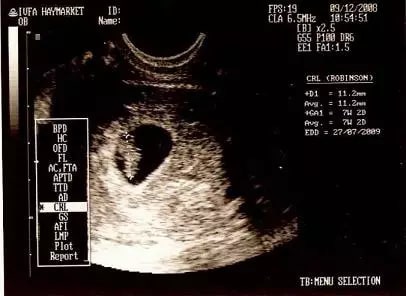

1、仅限8周之前的B超单

孕囊要看早期形状,40-50天左右是最准的,如果是9周以后的数据准确性就很低了,妈妈们快翻翻早期的B超单。

2、需要有孕囊的3个边长数据

很多妈妈的B超单上只有两个数据,比如4.0cm*2.6cm,这只是横截面的数据,不能用来看男女,很多妈妈看错就是这个原因。只有3个数的数据才能看,比如4.0cm*3.8cm*2.6cm。